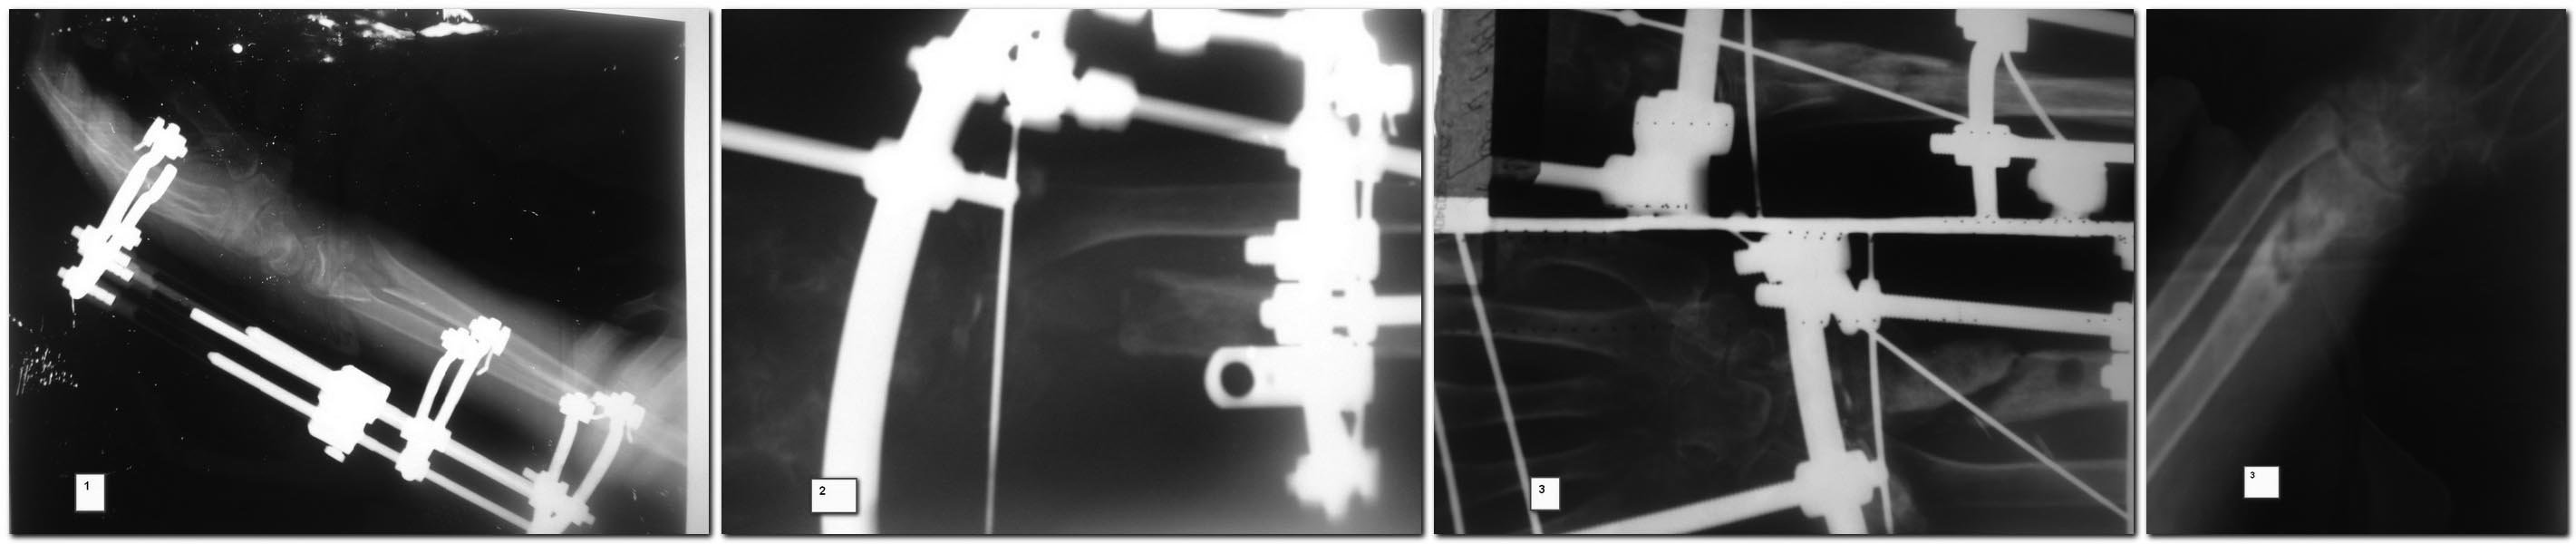

Здравствуйте уважаемые коллеги, просим Ваше мнение по поводу лечения ложного сустава дистальной части лучевой кости после костной пластики и остеомиелита Женщина 55 лет, травма 8 мес назад, был открытый перелом дистального метаепифиза правой лучевой кости А2, осложненный флегмоной предплечья через неделю после травмы. К нам обратилась через 1 мес после травмы, с иммобилизацией перелома в АВФ (снимок 1) и свищом с гнойными выделениями. Нами произведена резекция кости в пределах здоровых тканей ( около 3 см) проксимально 8 см на фоне здоровой трубчатой кости в канале густой эксудат темного цвета, который эвакуирован и все промыто антисептиками ( снимок 2). Установлены бусы с антибиотиком. Рана полностью зажила через 1.5 мес, бусы удалены.3 месяца выждали, на фоне отсутствия воспаления выполнили костную пластику из крыла подвздошной кости, АВФ 2.5 мес (снимок 3), + гипс 1 мес. На сегодняшний день отмечается лучевая косорукость, пат подвижность в месте ложного сустава, отсутствие воспаления.План: костная пластика + LCP из переднего доступа, укорочение локтевой кости или удаление головки локтевой кости. Уважаемые коллеги, поделитесь пожалуйста мнением по тактике дальнейшего лечения пациентки. С уважением , Александр.

К Вашему вниманию СКТ